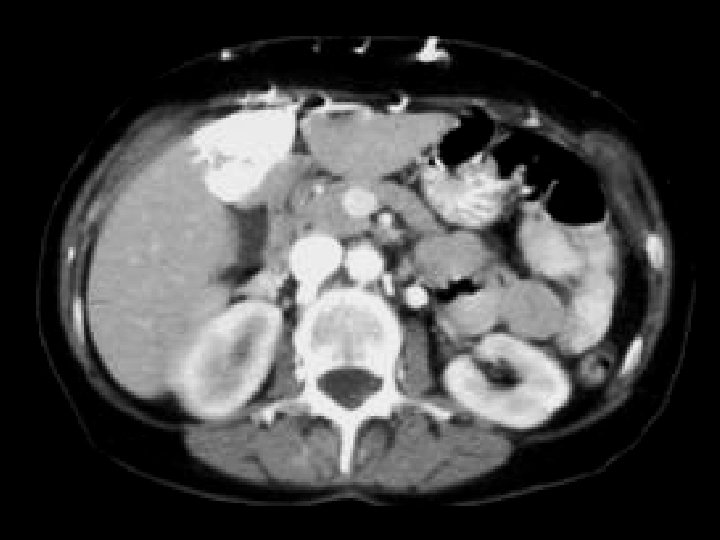

Von-Hippel Lindau • Findings: – Numerous bilateral renal cyst – Solid enhancing right renal mass = RCC • ddx: – NONE! – This is an Aunt Minnie!